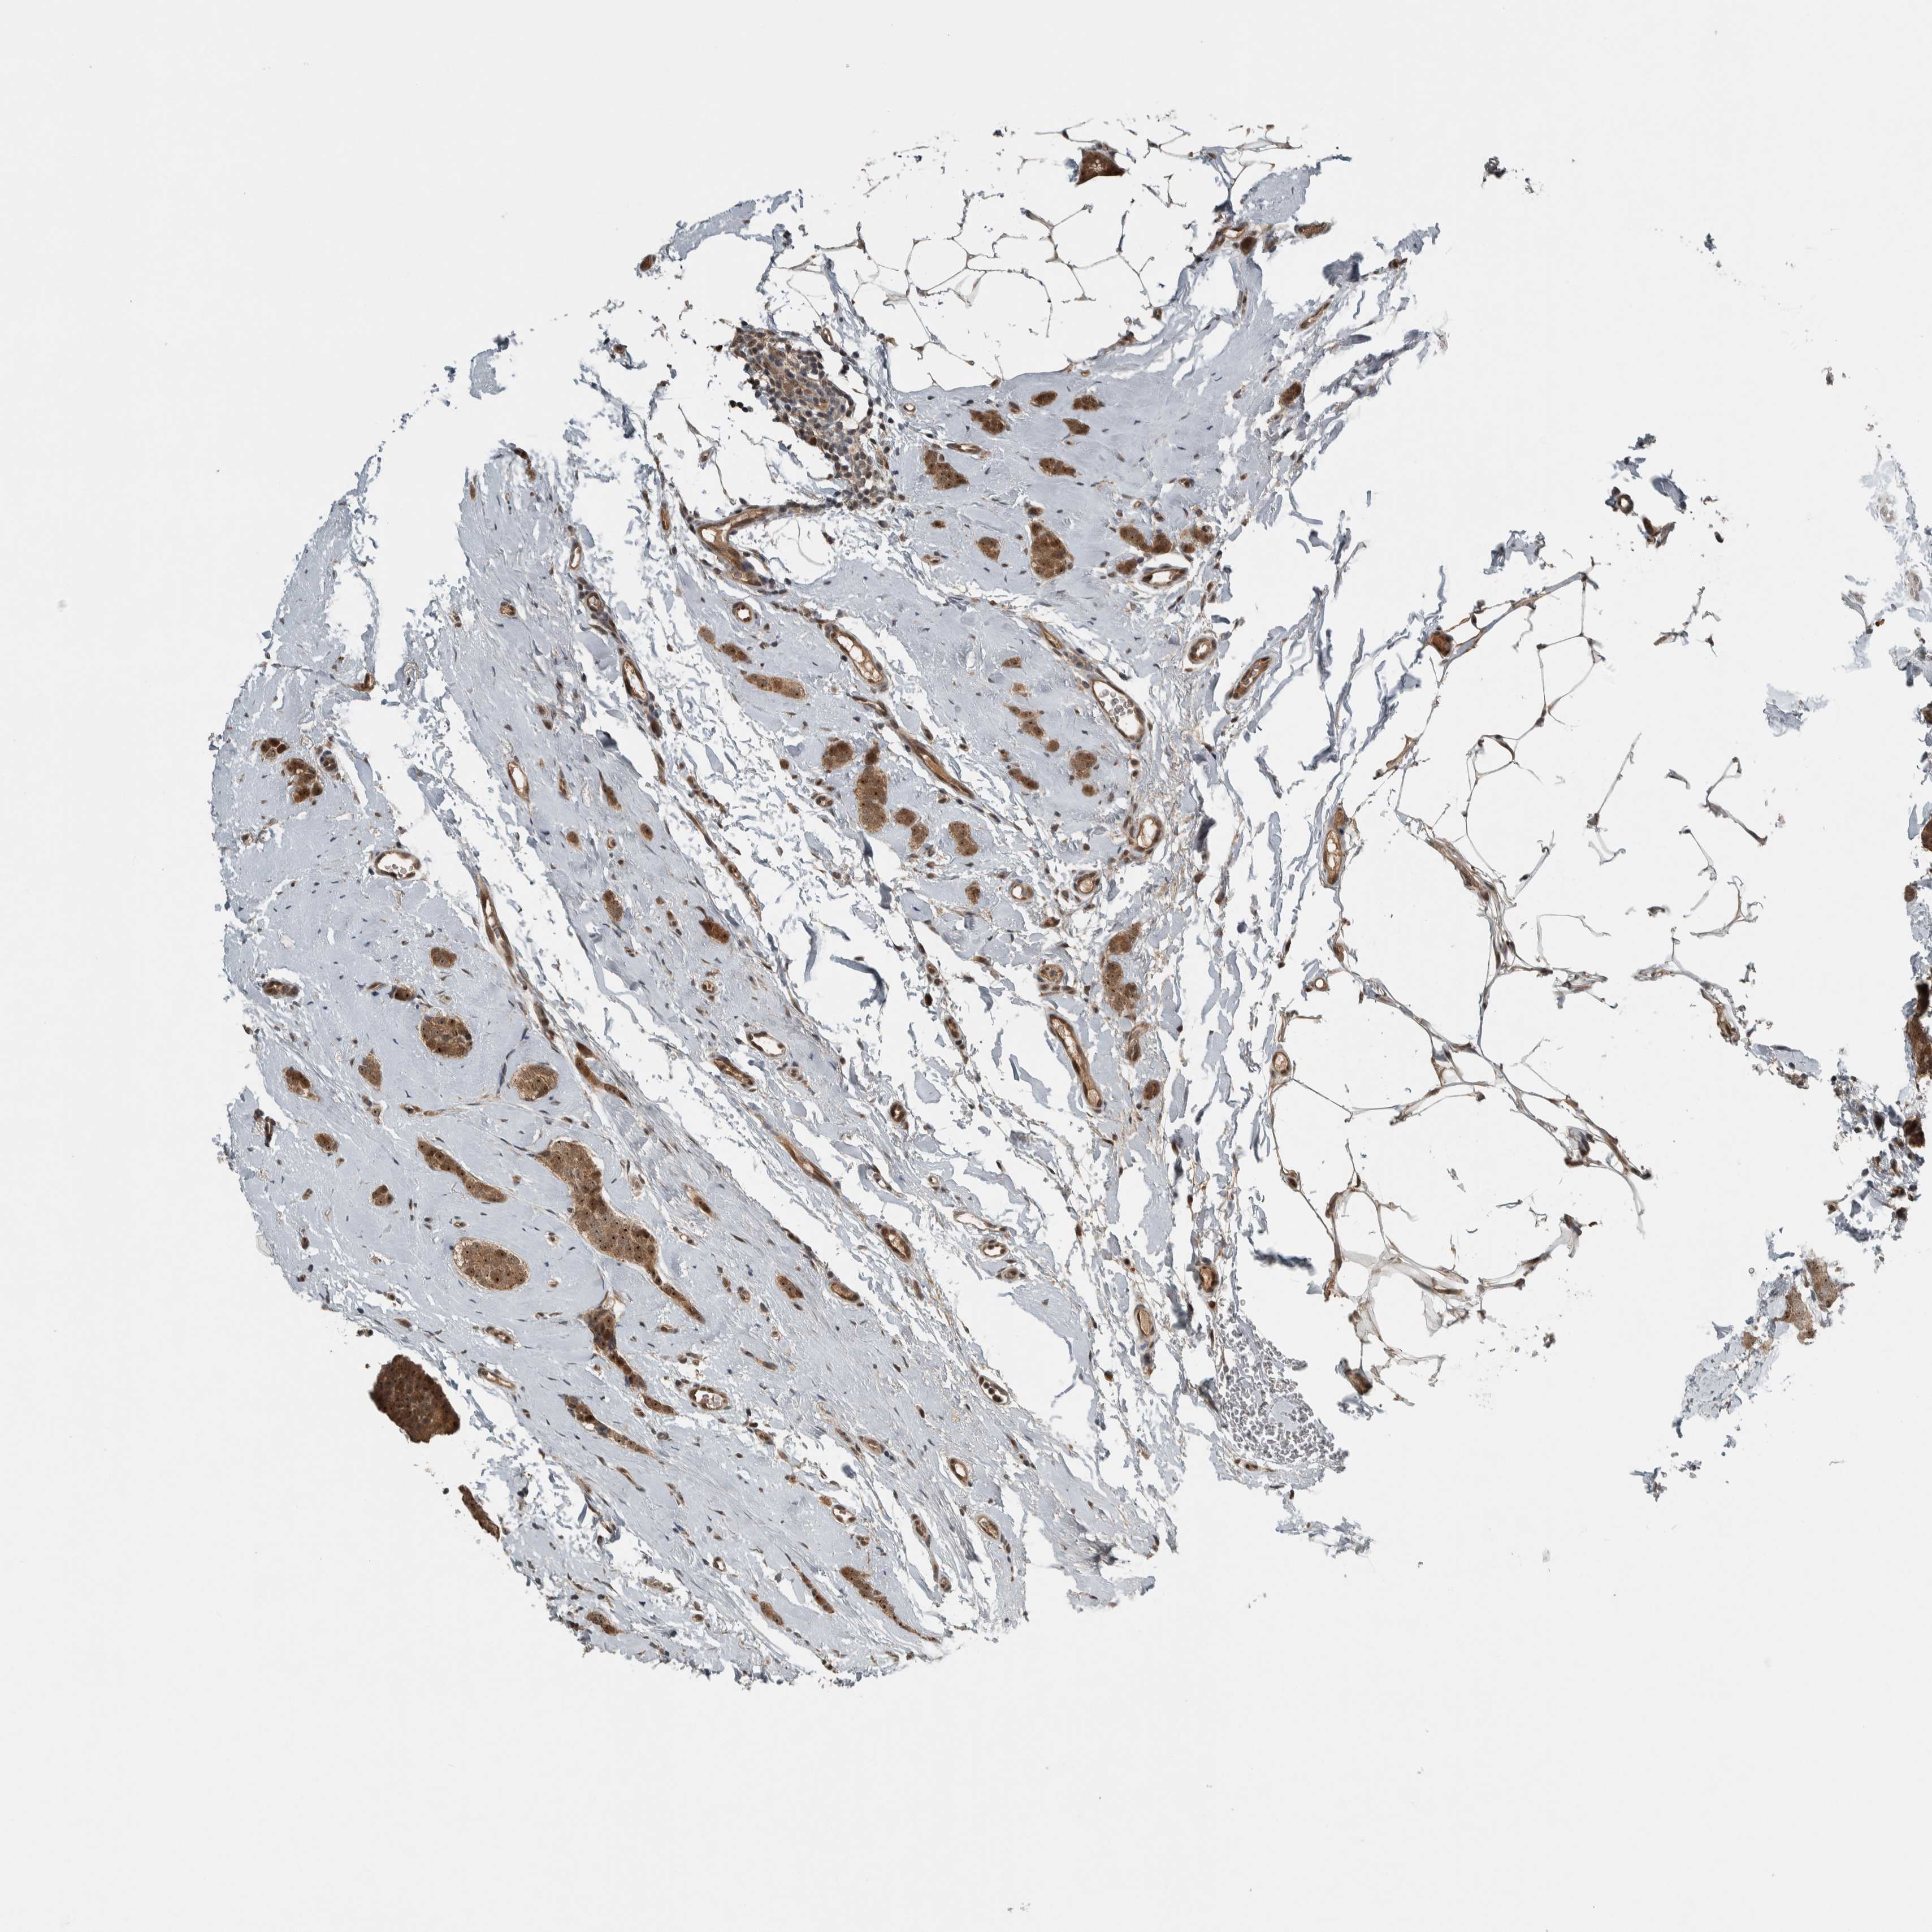

CANCER BREAST CANCER Show tissue menu

BRCA TCGA BRCA VALIDATION PROTEIN EXPRESSION